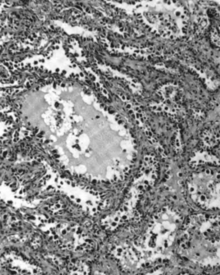

Micrograph of a mucinous ovarian carcinoma stained by H&E.

Mucinous adenocarcinoma

Mucinous adenocarcinomas make up 5–10% of epithelial ovarian cancers. Histologically, they are similar to intestinal or cervical adenocarcinomas, and are often actually metastases of appendiceal or colon cancers. Advanced mucinous adenocarcinomas have a poor prognosis, generally worse than serous tumors, and are often resistant to platinum chemotherapy, though they are rare.[18]